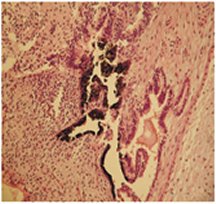

Starting with 185 donated eggs, the researchers successfully created 31 embryos carrying DNA from the various patients. Embryos representing 9 of the 11 patients yielded stem cells that survived in a lab culture. Hwang’s team found that the stem cells and the patients’ original cells have the same markers that the immune system uses to distinguish self from foreign cells. After several weeks, clumps of the new stem cells grew into different tissue types, showing that they can create many of the body’s different cells, the researchers assert.